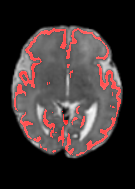

Fetal cortical plate segmentation is essential in quantitative analysis of fetal brain maturation and cortical folding. Manual segmentation of the cortical plate, or manual refinement of automatic segmentations is tedious and time-consuming. Automatic segmentation of the cortical plate, on the other hand, is challenged by the relatively low resolution of the reconstructed fetal brain MRI scans compared to the thin structure of the cortical plate, partial voluming, and the wide range of variations in the morphology of the cortical plate as the brain matures during gestation. To reduce the burden of manual refinement of segmentations, we have developed a new and powerful deep learning segmentation method. Our method exploits new deep attentive modules with mixed kernel convolutions within a fully convolutional neural network architecture that utilizes deep supervision and residual connections. We evaluated our method quantitatively based on several performance measures and expert evaluations. Results show that our method outperforms several state-of-the-art deep models for segmentation, as well as a state-of-the-art multi-atlas segmentation technique. We achieved average Dice similarity coefficient of 0.87, average Hausdorff distance of 0.96 mm, and average symmetric surface difference of 0.28 mm on reconstructed fetal brain MRI scans of fetuses scanned in the gestational age range of 16 to 39 weeks. With a computation time of less than 1 minute per fetal brain, our method can facilitate and accelerate large-scale studies on normal and altered fetal brain cortical maturation and folding.